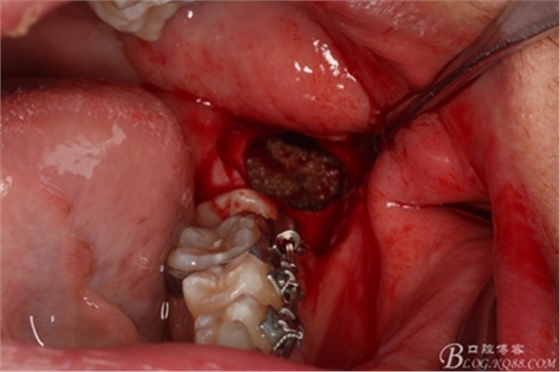

圖15.接著取出近中部分

圖16.清理38牙槽窩內(nèi)的囊壁及碎牙片

圖17. 38牙槽窩放入膠質(zhì)銀

18.縫合